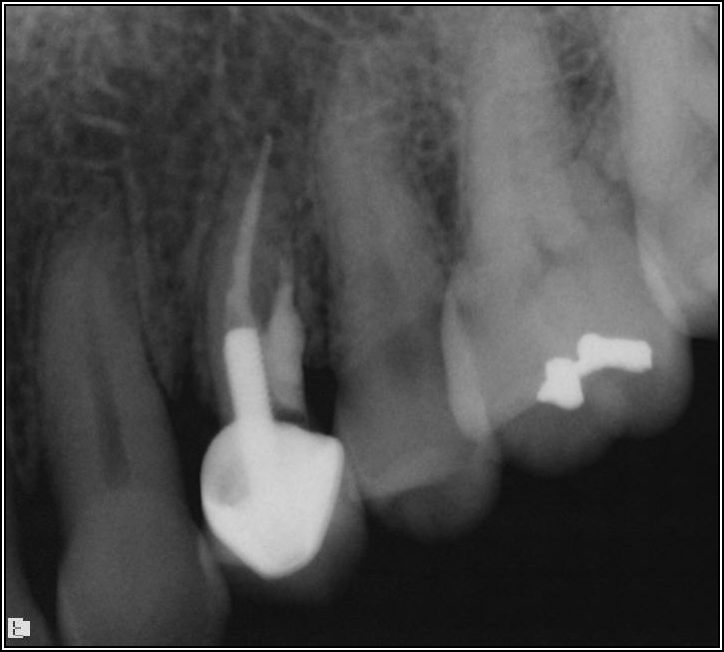

Figure 9 shows a situation on tooth No. 12 that may have been presumed to be easily resolvable. However, the dentist experienced problems, including significant bleeding. It was due either to irreversible pulpitis or a perforation. Judging by the PA, something detrimental was occurring with the distal. A lesson that can be learned from this case is that a solution does not have to look pleasant for it to work. Functionally, the repair shown in Figure 10 was successful because the clinician was able to fix the whole wall with mineral trioxide aggregate (MTA) and was able to find the canal. The clinician also put in the post for the general dentist and closed it. Later, the general dentist took the post out and replaced it with a post that was larger and shorter than would be recommended. Interestingly, the result lasted 8.5 years, as shown in Figure 11.

The clinician took the path described because the patient initially came in with some sensitivity on the tooth, but the issue quickly progressed to the need for a root canal and the possibility of losing the tooth because her general dentist had inadvertently destroyed the wall. Unfortunately, the story does not have a happy ending: at 9.25 years, the repairs finally broke. Yet the case is important because it shows that a resolution for even a “terrible” case can last almost 10 years and be to some extent a success. When the right principles are maintained, there can still be a successful outcome. The reason this case in particular succeeded was because of a factor that was barely visible: above the perforation repair was 2 mm of ferrule and, therefore, coronal tooth structure. The perforation was not only below the gum but also the bone, which is generally a more ideal location for a perforation.

Fig 10. Repair was initially successful.

Figure 10

Fig 11. The repair lasted 8.5 years.

Figure 11